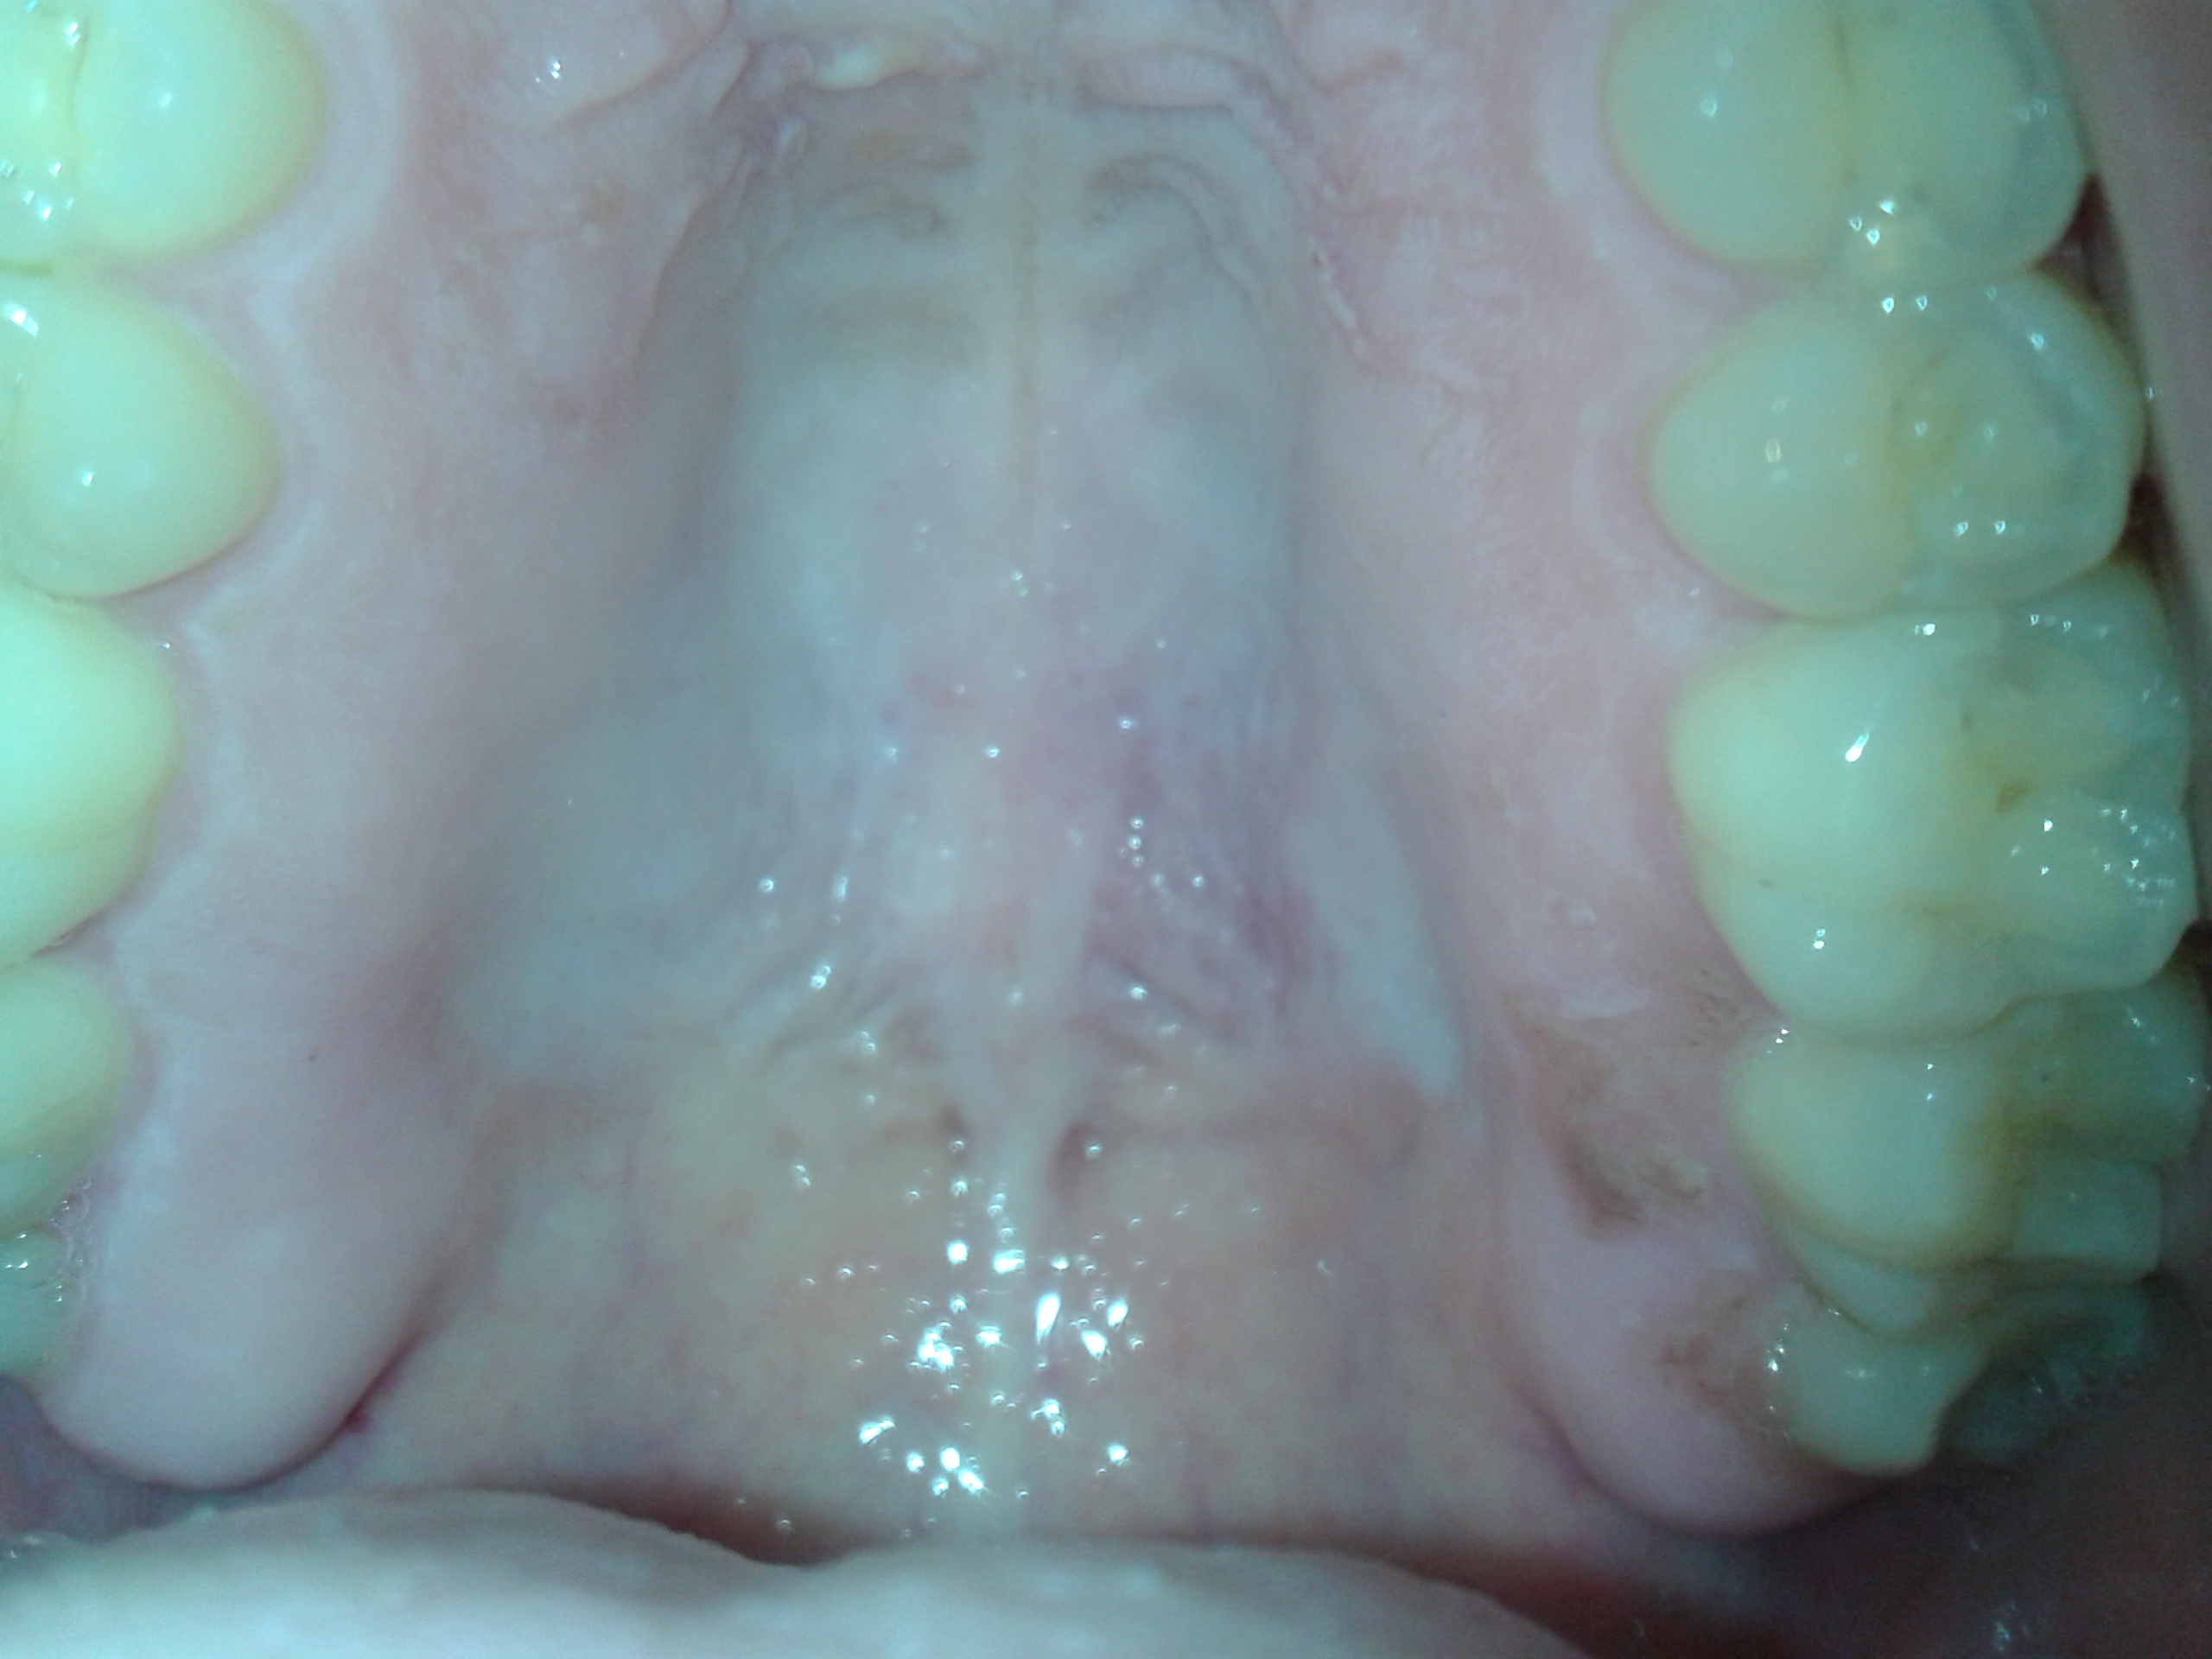

Dolore al palato molle